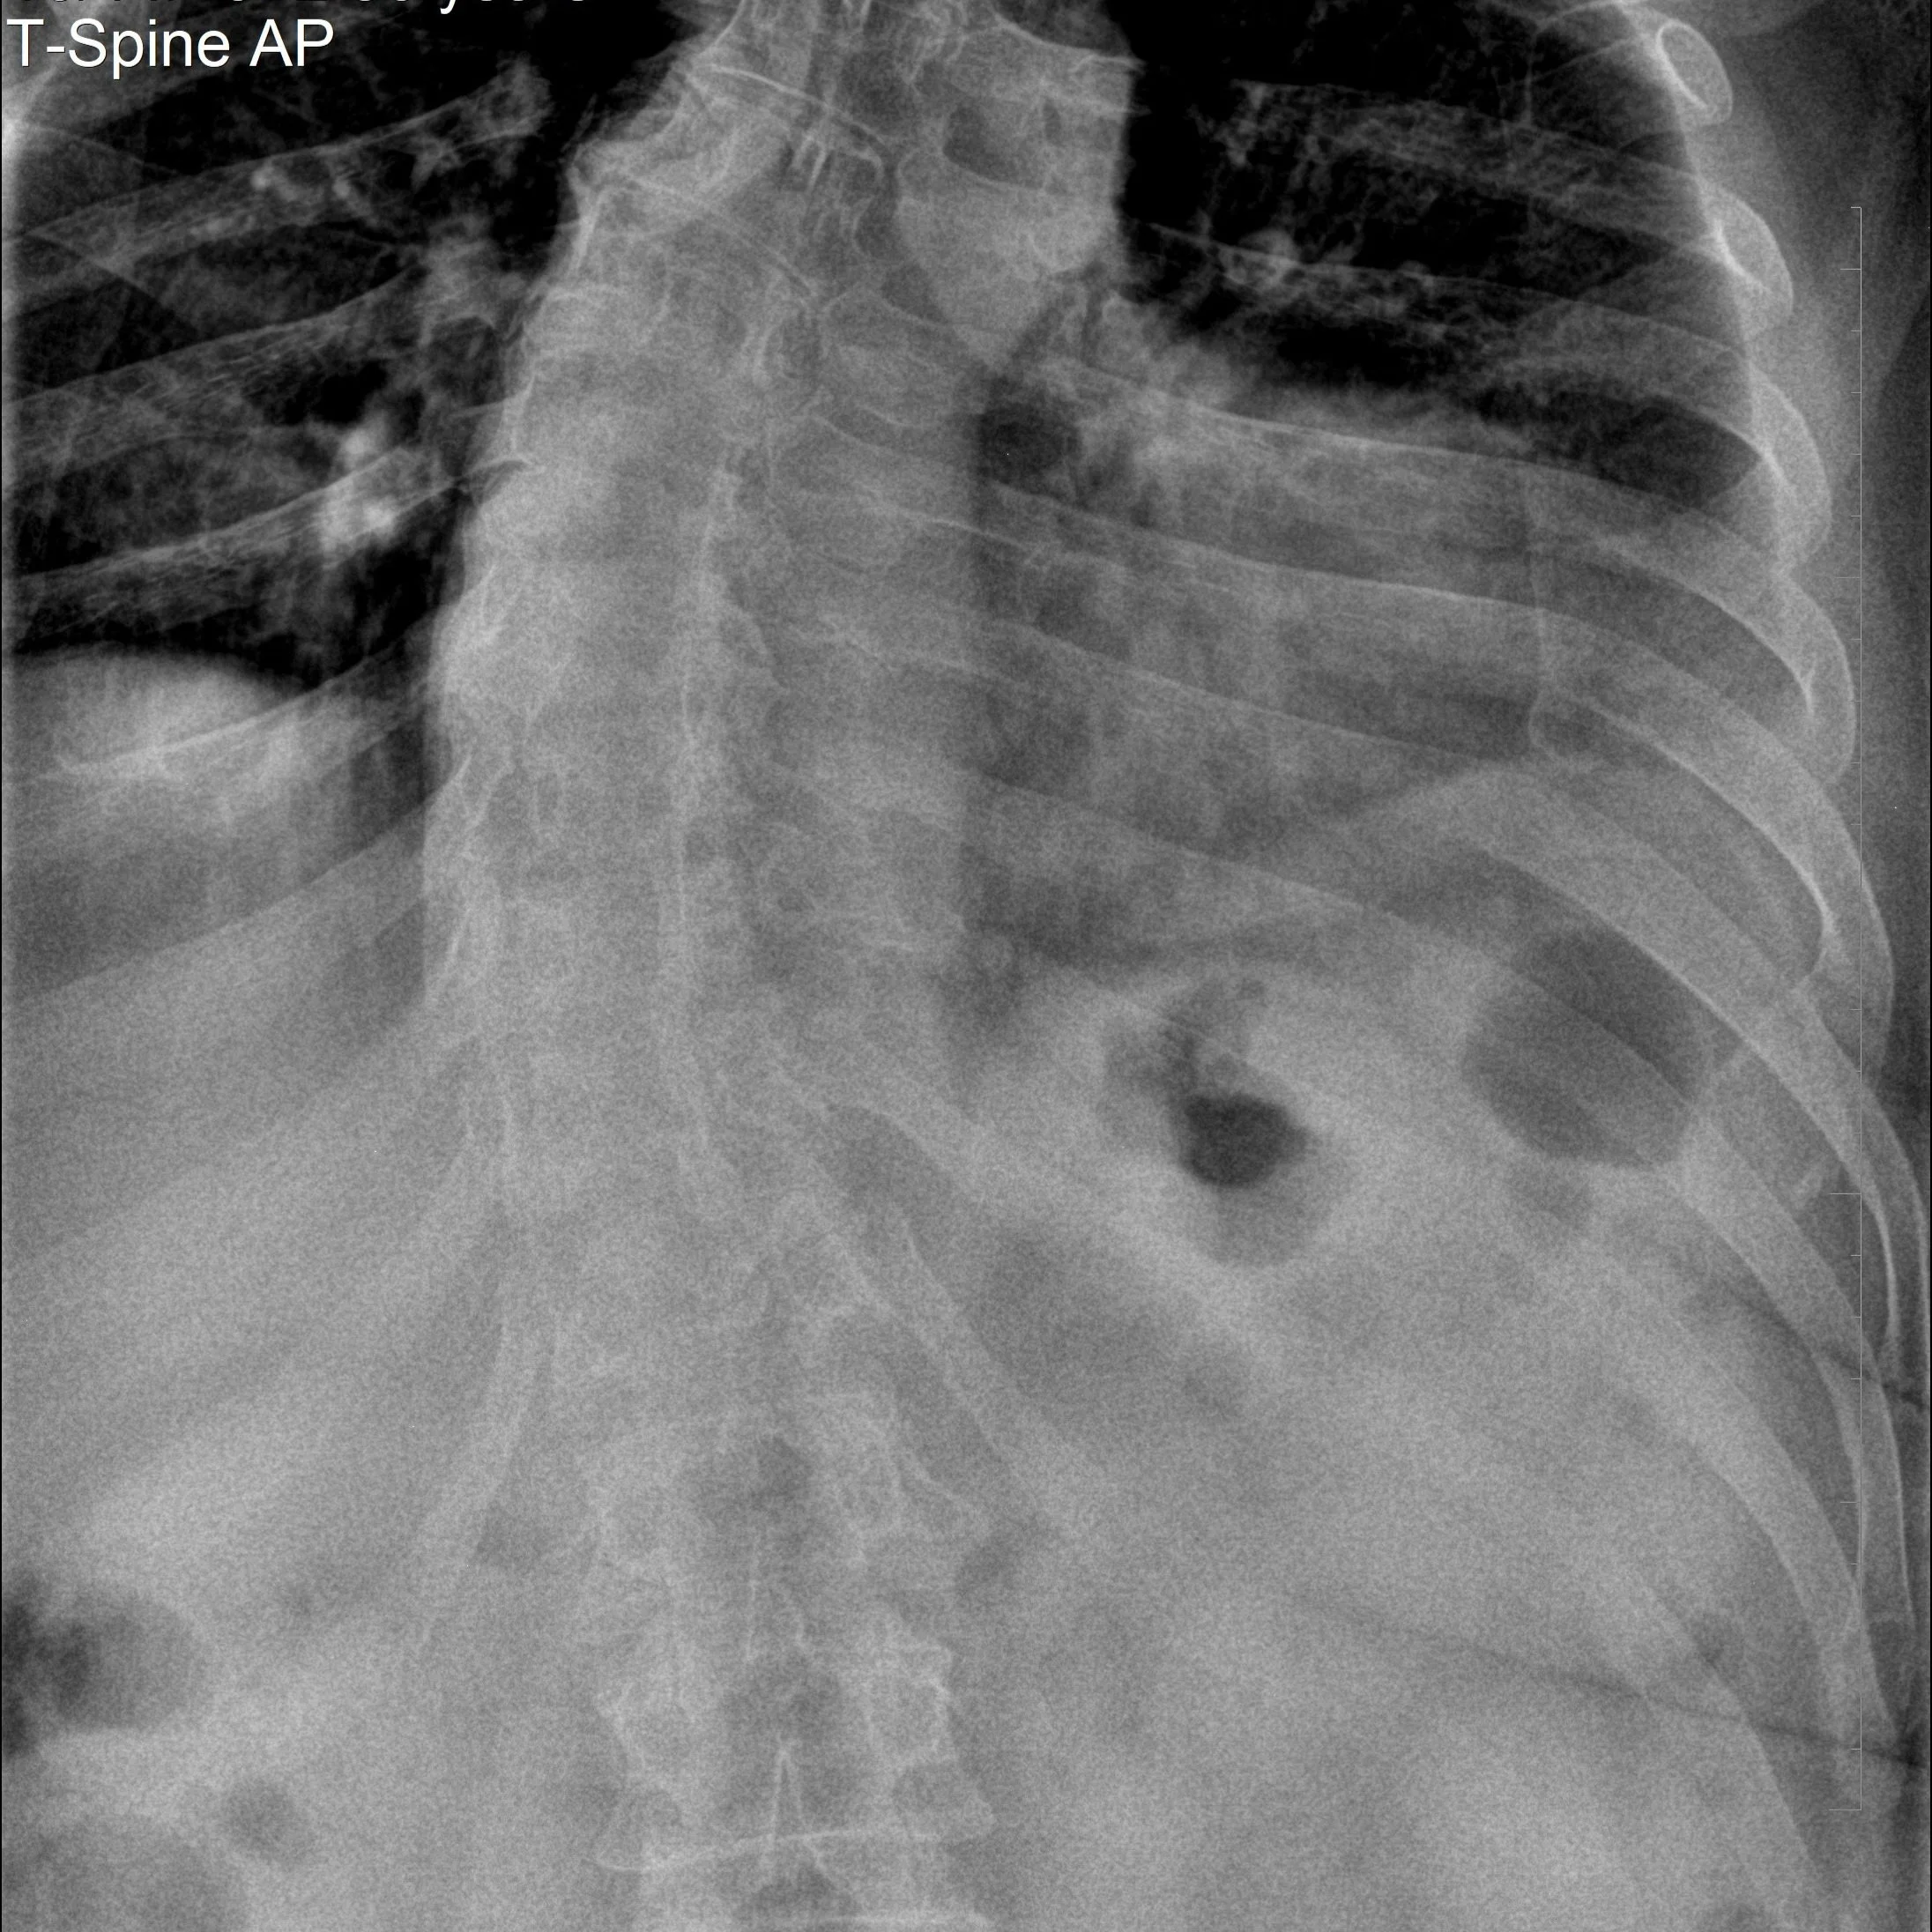

Thoracic scoliosis xray

Scoliosis is defined as a clinical curvature of the spine greater than 10 degrees when viewed from the front. This differs from a functional spinal curvature, which is typically subclinical, often resulting from posture, muscle imbalances, or habitual movement patterns. Functional curves are very common and occur in most people.

Scoliosis is typically identified through a combination of physical examination, orthopedic tests, and medical imaging. Clinical assessment may include observing posture, orthopedic testing, spinal alignment, and range of motion. If scoliosis is suspected, X-rays are commonly used to confirm the diagnosis and measure the degree of curvature. In some cases, further evaluation or referral to a specialist may be necessary for a more detailed assessment or to determine appropriate management.